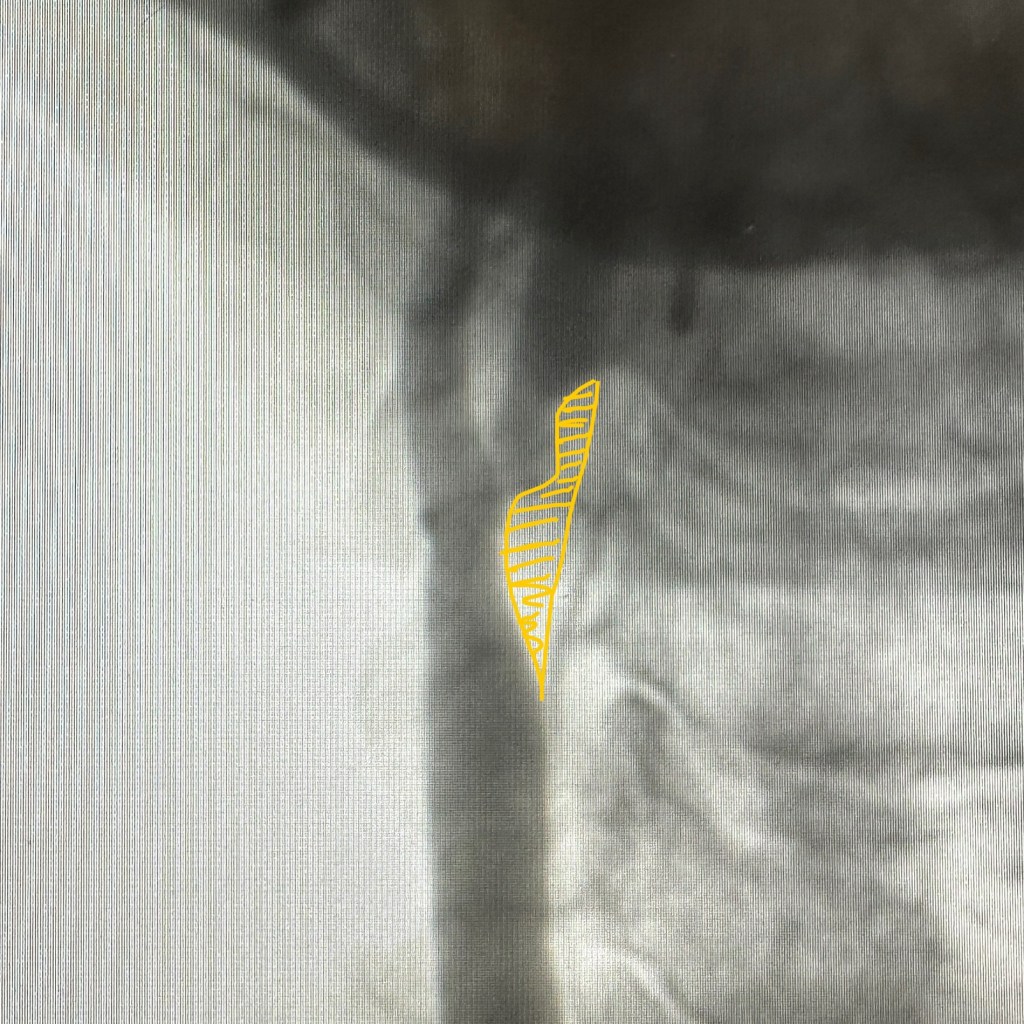

في الصور اللي معانا في هذا الموضوع:

– في الصورة الثانية: وهي نفس الصورة، أنا مظلّل باللون الأصفر الترسّبات الدهنية اللي عاملة الضيق… لما تشوفوها كده هتفهموا بالعين الموضوع ماشي إزاي.